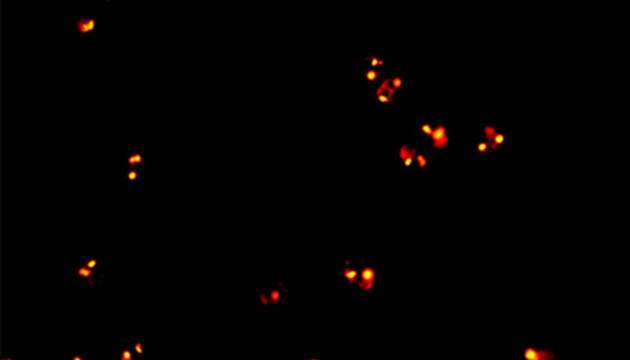

CTC檢測(cè)用于上皮腫瘤,如胃腸癌、皮膚癌等。檢測(cè)分四步:富集、CD45染白細(xì)胞、CK染CTC、DAPI染核。有DAPI、CK熒光且無(wú)CD45熒光,大核細(xì)胞為CTC;有DAPI、CD45熒光為白細(xì)胞。

MF43-N用于CTC檢測(cè)